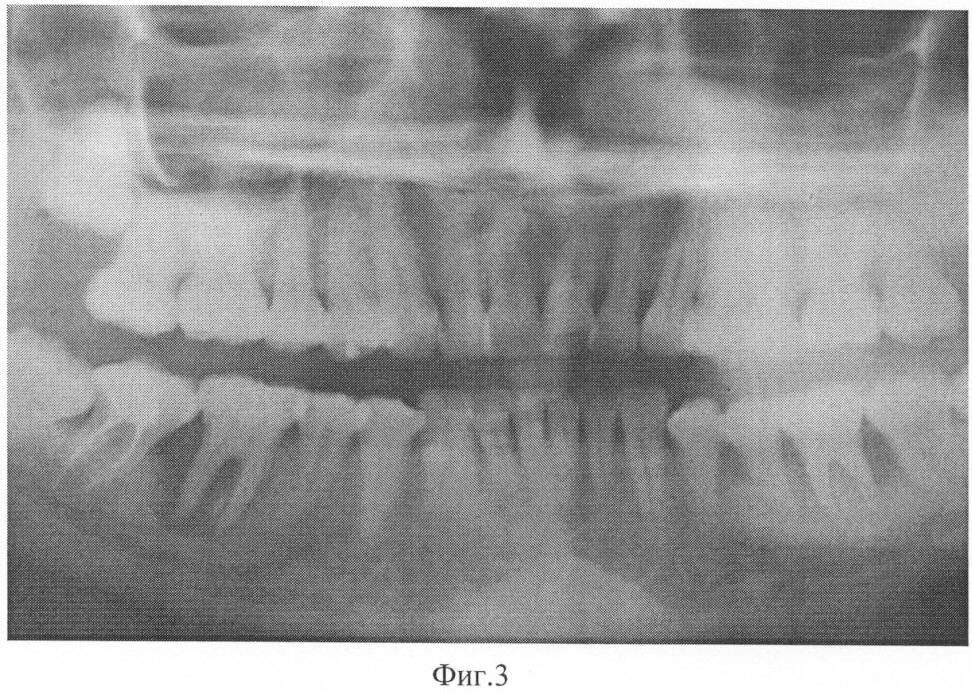

На фиг.1 представлена рентгенограмма пациента 1 до лечения заявленным способом.

Данные рентгенологического исследования. На ортопантомограмме верхней и нижней челюстей определяется убыль костной ткани межальвеолярных перегородок за счет резорбции на 1/2 и более длины корня в области зубов верхней челюсти и более 2/3 длины корня в области нижних зубов. В области 47, 36 зубов диагностируется резорбция костной ткани округлой формы с четкими границами, клинически соответствующая пародонтальным кистам, выходящим за пределы корня зуба.

Больному было проведено комплексное лечение, включающее обучение гигиене полости рта, санация некачественно запломбированных каналов, снятие поддесневых зубных отложений и кюретаж пародонтальных карманов, проведение антибиотикотерапии (сумамед 250 мг – 5 дней), удаление 27, 46, гемисекция в области 36, изготовление шинирующих конструкций и временных коронок на нижнюю и верхнюю челюсти. Сразу после проведения хирургического лечения (лоскутная операция с остеопластикой и введением препарата Остеопласт в область вертикальных костных дефектов) был назначен курс препарата Калькохель по одной таблетке три раза в день в течение трех недель, затем препарат Остеохель С по одной таблетке три раза в день в течение трех недель, затем перерыв три недели и повторно те же препараты тем же курсом. Повторное обследование проводили через 11 месяцев после начала лечения. Осмотр полости рта показал следующее: слизистая оболочка десны бледно-розового цвета, без признаков кровоточивости, глубина пародонтальных карманов в пределах 3 мм в области всех зубов. На ортопантомограмме определяется закрытие вертикальных костных дефектов полноценной костной тканью, восстановление формы межзубных перегородок и появление четкой кортикальной пластинки по краю кости.

Сам пациент отмечает значительное улучшение состояния, исчезновение кровоточивости десен и подвижности зубов, отсутствие рецидивов заболевания более 3 лет. Пример подтверждается рентгенограммами, выполненными до лечения – фиг.1 и после лечения – фиг.2.